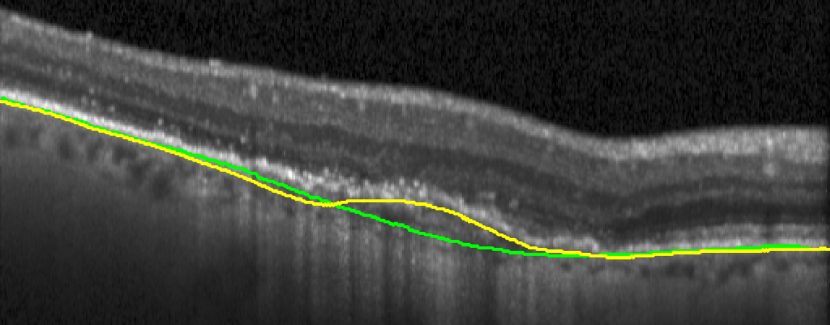

Bruch’s Membrane is an elastic smooth and thin structure, strategically located between the retina and the general circulation, having a crucial role in retinal function, aging and disease [14]. Automated segmentation of the BM is particularly important in the context of AMD as, unlike other common retinal diseases such as DR, RVO, or glaucoma, the BM is distinguishable from the outer RPE boundary. In specific, drusen in iAMD and PEDs in nAMD separate the RPE from BM, requiring the segmentation of the region in-between them. In addition, in case of GA, the RPE is completely lost in some locations, exposing only the BM, thus imposing additional difficulties for algorithms and calculations that depend on the RPE position. Achieving correct automated identification of the BM is challenging in many cases, mainly due to the small thickness of this layer, the high reflectivity of the RPE that shadows parts of the BM, and the noise being present in the scans, which is often indistinguishable from the content of drusen and PEDs (Fig. 4). Due to these difficulties, currently many automated solutions either do not provide a segmentation of the BM or its segmentation is often inaccurate in retinal OCT with AMD, leaving this clinically relevant segmentation task unaddressed or under-explored.

(a) iAMD

(b) nAMD

(c) GA